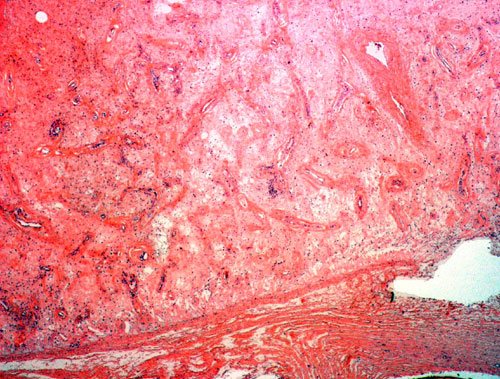

Histopathology: Panel B is taken at the periphery of the tumor where a well circumscribed margin is demonstrated. The tumor has rich vascularity and a hypocellular stroma. However, increased stromal cellularity is present in some areas.  Hyalinized blood vessels and a sclerotic to edematous stroma are well demonstrated in Panel C. Also present are a few lymphocytes clustering around blood vessels. The sclerotic stroma with edema and sparse lymphocytic infiltration is demonstrated in Panels D and E. The bland cytologic features are shown in Panel F.

Macroscopically, AMFBs range from 0.5 cm to 14 cm in greatest dimension with the majority of them between 2-8 cm. The lesions are well-circumscribed, round, ovoid, or lobulated masses with a soft to rubbery consistency. The cut surface varies from gray-pink to yellowish brown to tan and is of homogeneous texture with focal myxoid areas. Microscopically, the margin is well delineated and non-infiltrative. A complete or partial fibrous pseudocapsule of varying thickness may be present. Some tumors are bordered in part by mature adipose tissue or smooth muscle. The tumor is characterized by rich vascularization in a background of collagenous to edematous stroma with alternating hyper- and hypocellular regions 3. The stromal background is edematous rather than myxoid. The nature of the background is supported by negative staining for Alcian blue stain.